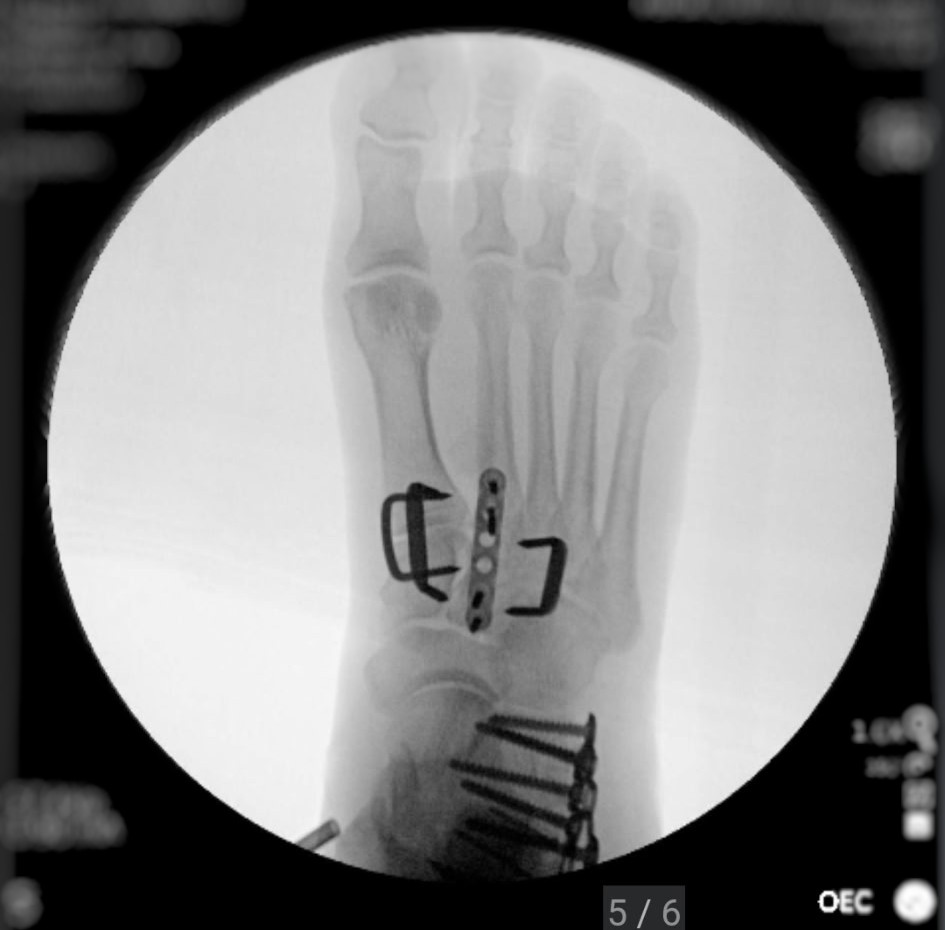

Hello, I am sure many of you have heard the news of Anita Featherstone (Morris) being involved in a head-on accident with a drunk driver. On Sunday afternoon, March 30th, she was leaving the Crosby/Houston area, heading to visit her daughter and grandsons. She was driving and missed her turn, and she was rerouted down a two-lane road she doesn't normally travel. As she was driving, she saw a car headed towards her in the other lane. She saw his tire slip off the road, and then everything went black. The next thing she remembers is waking up in the car (thinking she was dying). She was struggling to breathe and was in severe pain. With the help of a "good samaritan" that yielded, he was able to help her get out of the car and contact her family. She was not able to walk as part of her foot was missing with the bone exposed. Her sons (Michael & Matthew) arrived at the scene moments later and were informed by the responding officers that she was hit by a drunk driver and would need to be airlifted to Memorial Hermann Medical Center. She arrived at the hospital and was immediately rushed to trauma where they performed X-rays and CT scans to determine the extent of her injuries. She sustained major injury to her right foot and hand, with her right foot having a compound fracture with the heel crushed and her right hand also fractured. They were able to splint her hand but required emergency surgery on her right foot. She had many other contusions and bruises all over her body. She went into surgery several hours later where they cleaned out the wound, performed a nerve block, and set the foot. This is only step one in a very long road to recovery. She will need to have at least two more surgeries on her right foot. Her next surgery will not happen for at least two weeks because the swelling must go down. She is not able to put pressure on her right foot for two months. She will require physical and occupational therapy to learn how to walk again. Due to the nature of the injuries, she will not be able to use a walker, crutches, or a scooter for a couple of months. Unfortunately, the individual that hit her was driving an unregistered vehicle without insurance and has no license. He also was undocumented. Thankfully, they confirmed with blood tests that he was intoxicated, and Harris County will be bringing charges. Anita is self-employed and will not be able to work for months, and her medical bills are already piling up. Anything you can give would be much appreciated. Thank you all for hearing our story. God bless.